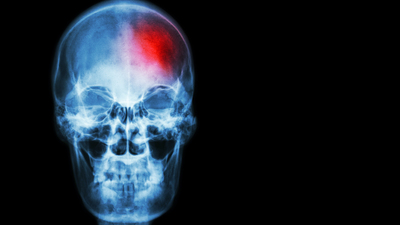

İnme artık kader değil, tedavi edilebiliyor!

Ülkemizde her yıl yaklaşık 200.000 kişi inme geçiriyor. Her 40 saniyede bir kişi inme geçiriyor; üç dakikada bir kişi ise inme nedeniyle yaşamını yitiriyor. İnme son 20 yıla kadar Dünya Sağlık Örgütü listesinde ölüm nedenleri arasında 3. sırada yer alıyordu. Ancak özellikle son 20 yıldır tanı ve tedavi alanında hızlı gelişmeler sayesinde tedavi edilebilir bir hastalık durumuna geldi. Bu nedenle tedavinin başarılı olması için erken davranmak hayati önem taşıyor. Acil durumlarda hızlı ve başarılı tedavi için inme konusunda deneyimli merkezlerin belirlenmesi ve acil hizmetinin hastaları bu merkezlere ulaştırmaları gerekiyor. İnme tedavisi, hem sürecin iyi değerlendirilmesi ve hem de kullanılacak tedavi yöntemlerinin hastadan hastaya değişkenlik göstermesinden dolayı kişiye özgü bir tedavidir. İnme ile mücadelede tek bir hekim değil; multidisipliner, konusunda yetkin bir ekip birlikteliği büyük önem taşır... Prof. Dr. Derya Uludüz yazdı

Tıpta zamana karşı yarıştığımız hastalıklar vardır, inme de bu hastalıklardan bir tanesi... Her geçen zaman beyindir diyoruz çünkü zaman geçtikçe sağlık merkezine ulaşmaya ne kadar gecikirsek beynimizin bir parçasını kaybediyoruz, inme böyle bir hastalık. Bizlerden uzak gibi görünüyor, oysaki çok yakınınızda olabilir. Herkesin başına her an gelebilir. Bugün engelli değiliz ama yarın olabiliriz. Özellikle risk grubunda olan kişiler bu açıdan oldukça önemli...

İnme tedavisi girişimsel anlamda yeni bir yaklaşım, pıhtı oluştuktan sonra oksijensizliğe hassas beyin dokusunu kurtarmak ve oluşacak hasarı önlemek gerekiyor. İnme geçirdikten sonra her geçen dakika milyonlarca hücre ölümü demektir. Toplardamar yolu ile pıhtı eritici tedavilerin inmenin ilk 4.5 saatinde, beyin anjiografisi yapılarak damarda pıhtının çıkartılması yöntemi yani mekanik pıhtı çıkarma yöntemi ise ilk 8 saatte hastaya mutlaka uygulanmış olması gerekiyor. Tedavi ilk 3 saatte yapıldığında 7 hastanın birinde, ilk 4.5 saat içinde yapıldığında 11 hastanın 1 tanesi tamamen iyileşiyor.